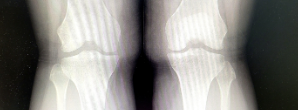

무릎 류마티스 관절염이란 무릎 관절에 염증이 생겨 통증, 부기, 뻣뻣함, 그리고 관절의 기능 상실을 일으키는 만성 염증성 질환입니다. 이 질환은 면역체계가 건강한 관절 조직을 공격하기 때문에 자가면역질환으로 분류됩니다